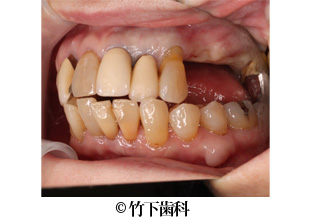

【症例3】右上臼歯部3本欠損のインプラントによる治療

- 治療前

- 治療後

- 治療名

- 右上臼歯部3本欠損のインプラントによる治療

- 費用

- 825.000円(税込)

【内訳】

骨造成は以下に含む

インプラント埋入術 220,000円×3

インプラント上部構造 55,000円×3

- 期間

- 9ヵ月

- 通院回数

- 12回

- 患者様

- 60代女性

治療内容

患者様の症状

歯周病によって、右上5番は動揺が強いために抜歯しました。右上4番、6番は10年以上前に他医院にて抜歯済みでした。いろいろなものを奥歯で食べたいという希望があり、インプラント治療を希望されました。

治療法

右上の5番を抜歯してから2か月後にバーティカルサイナスアプローチによる骨造成をして、同時にインプラントを3本埋入しました。6ヵ月後にインプラントが強固に定着されたのを確認し、3本連結のジルコニアクラウンを装着しました。連結にしたことで、かむ力を分散させて骨への負担を減らしています。

治療結果

審美的にも機能的にも患者様の希望に添えた治療になりました。

そのほか

上顎洞歯槽骨の厚みが3mmしかなく、バーティカルサイナスアプローチにより5mm挙上して8mmのインプラントを埋入することができました。

※治療結果は患者様によって個人差があります。

治療を行う上での 注意点 (リスク・副作用)

出血、腫脹、疼痛、神経麻痺、補綴物のダツリ、破折、インプラント体の破折、咬合違和感、インプラント周囲炎